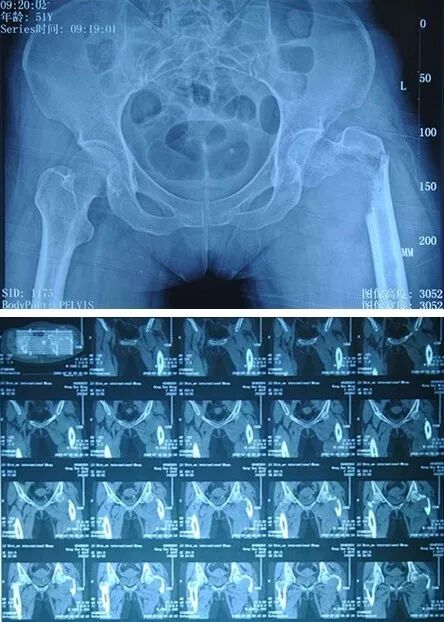

患者周小姐,24歲,在無明顯誘因下出現(xiàn)雙髖關(guān)節(jié)疼痛、活動受限。經(jīng)人介紹,就診于省級知名骨科專家、邦爾骨科集團首席專家、嘉興邦爾骨科醫(yī)院院長趙凱教授專家門診,診斷為“雙側(cè)股骨頭壞死”,左側(cè)比右側(cè)嚴(yán)重??紤]到患者還年輕,無法進行髖關(guān)節(jié)置換術(shù),而且股骨頭壞死還是早期,壞死面積不大,為了提高患者的生活質(zhì)量,減輕疼痛,趙凱教授決定為周小姐進行“左側(cè)人工髖關(guān)節(jié)全關(guān)節(jié)表面置換術(shù)”。

在手術(shù)中只刮掉壞死的軟骨,用一種合金材料覆蓋在股骨頭表面,就像給患者的股骨頭上戴個“帽子”,從而最大限度地保留患者的股骨頭,使關(guān)節(jié)功能保持良好。

術(shù)后半年,患者因右側(cè)髖部疼痛再次求診于趙凱教授,要求右側(cè)進行手術(shù)治療。針對右側(cè)股骨頭壞死的病情,趙凱教授制定了針對性的手術(shù)方案,決定為周小姐進行“右側(cè)股骨頭壞死人工鉭棒植入術(shù)”,這種手術(shù)方式非常適合青壯年的保髖治療,而且并不影響后期進行髖關(guān)節(jié)置換術(shù),為病人爭取了時間。

術(shù)后周小姐髖部疼痛消失,手術(shù)獲得極大成功,免除了年輕股骨頭壞死患者進行關(guān)節(jié)置換的需要。

術(shù)前顯示:雙側(cè)股骨頭壞死

術(shù)后右側(cè)鉭棒植入,左側(cè)假體位置良好